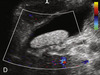

Barro biliar y 2 cálculos

Vesícula llena de barro biliar

Bola de barro biliar

Bola de barro biliar (sin flujo)